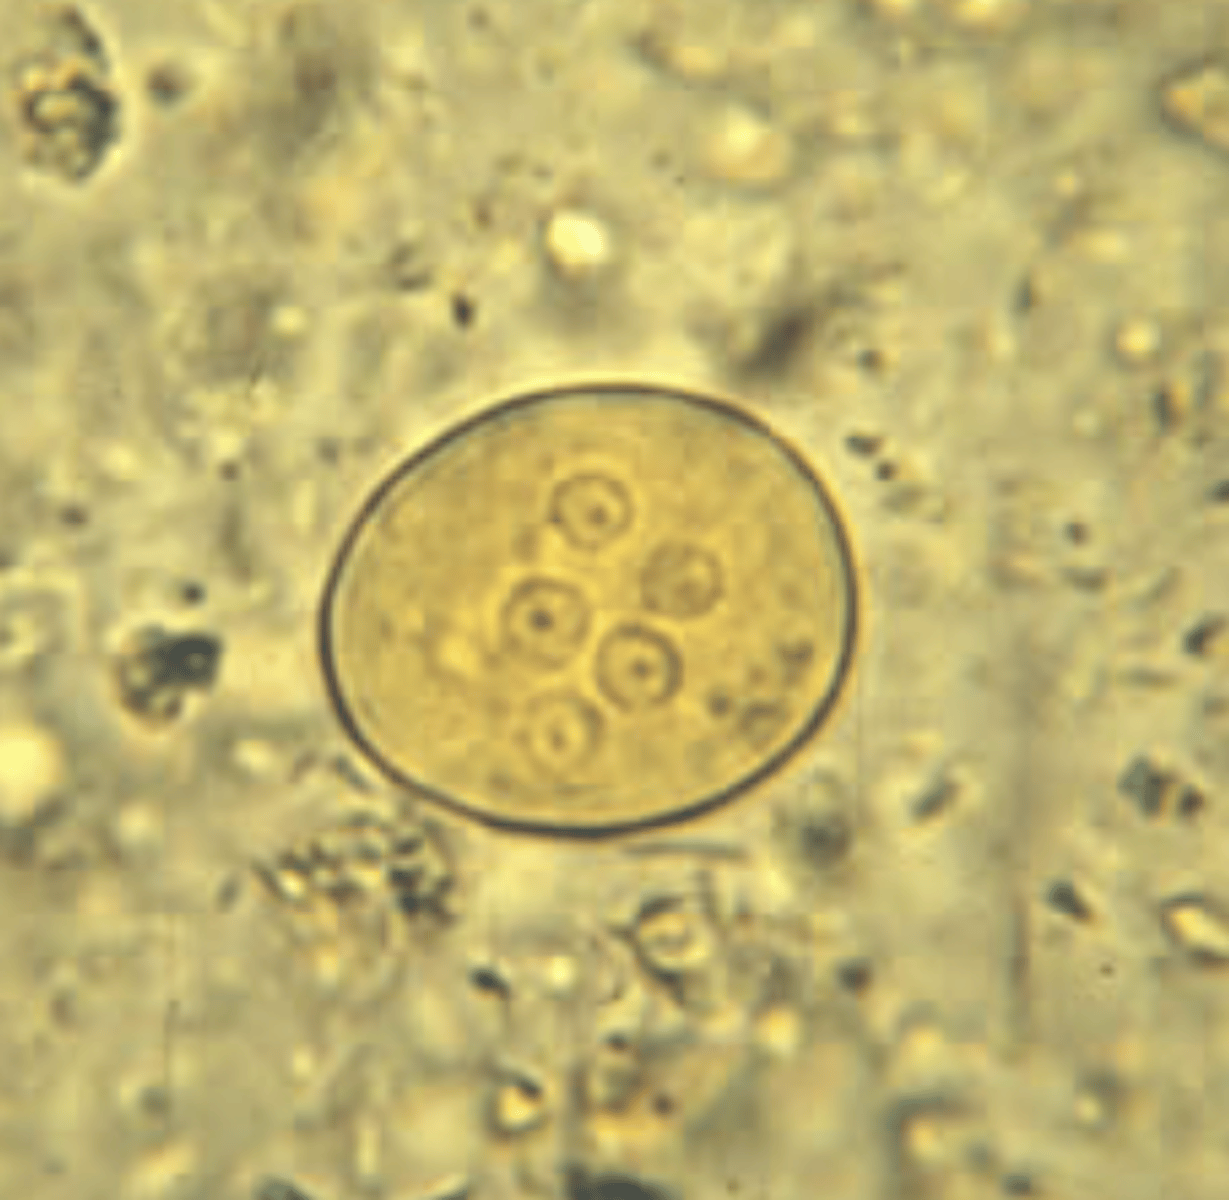

Giardia lamblia cyst